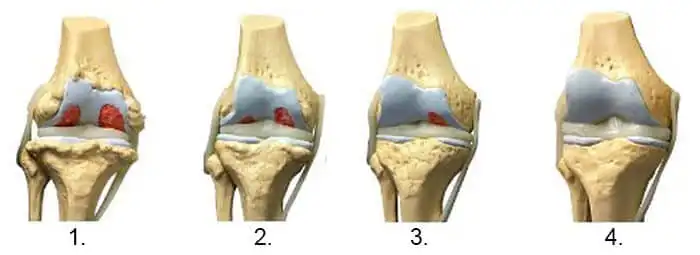

A térd ropogása nem az életkor jele – hanem segítségkérés az ízületektől

• Ropogás a térdben

Az ízületi fájdalom nem csak kellemetlen. Ha nem kezelik időben, teljesen elveheti a mozgás örömét és elszigetelheti az embert a szeretteitől.

Fontos megérteni: az ízület egy mechanizmus. Ha nincs kenőanyag, akkor tönkremegy. A Hondrofrost azért érdekes, mert összetétele segít a szervezetnek fenntartani a természetes regenerációs folyamatokat. Gyakran ajánljuk hatékony házi gyógymódként.